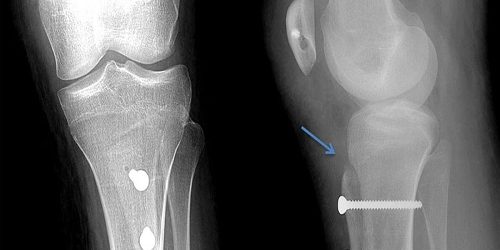

Tibial başlık, genellikle tibia adı verilen kaval kemiğinin üst ucu veya çıkıntısı olarak adlandırılır. Bu başlık, diz eklemi içinde femur (uyluk kemiği) ile temas eder ve diz eklemi hareketlerinde önemli bir rol oynar.

Tibial Başlık ve Ortopedideki Rolü

Tibial başlık, diz eklemi anatomisi ve hareketi açısından kritik bir yapıdır. Diz eklemindeki kıkırdak hasarı, menisküs yırtıkları ve diğer diz problemleri genellikle tibial başlık bölgesinde ortaya çıkar. Bu nedenle, ortopedik incelemelerde ve tedavi planlarında tibial başlık önemli bir odak noktasıdır.